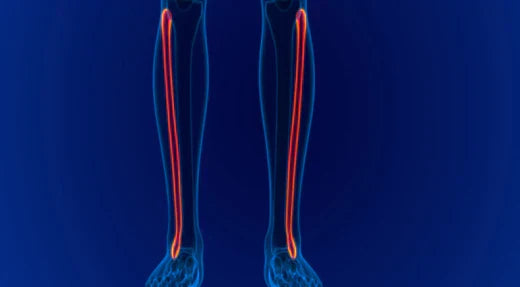

Understanding the Fibula: Structure, Function, ...

The fibula, also known as the calf bone, is a vital component of the lower leg.